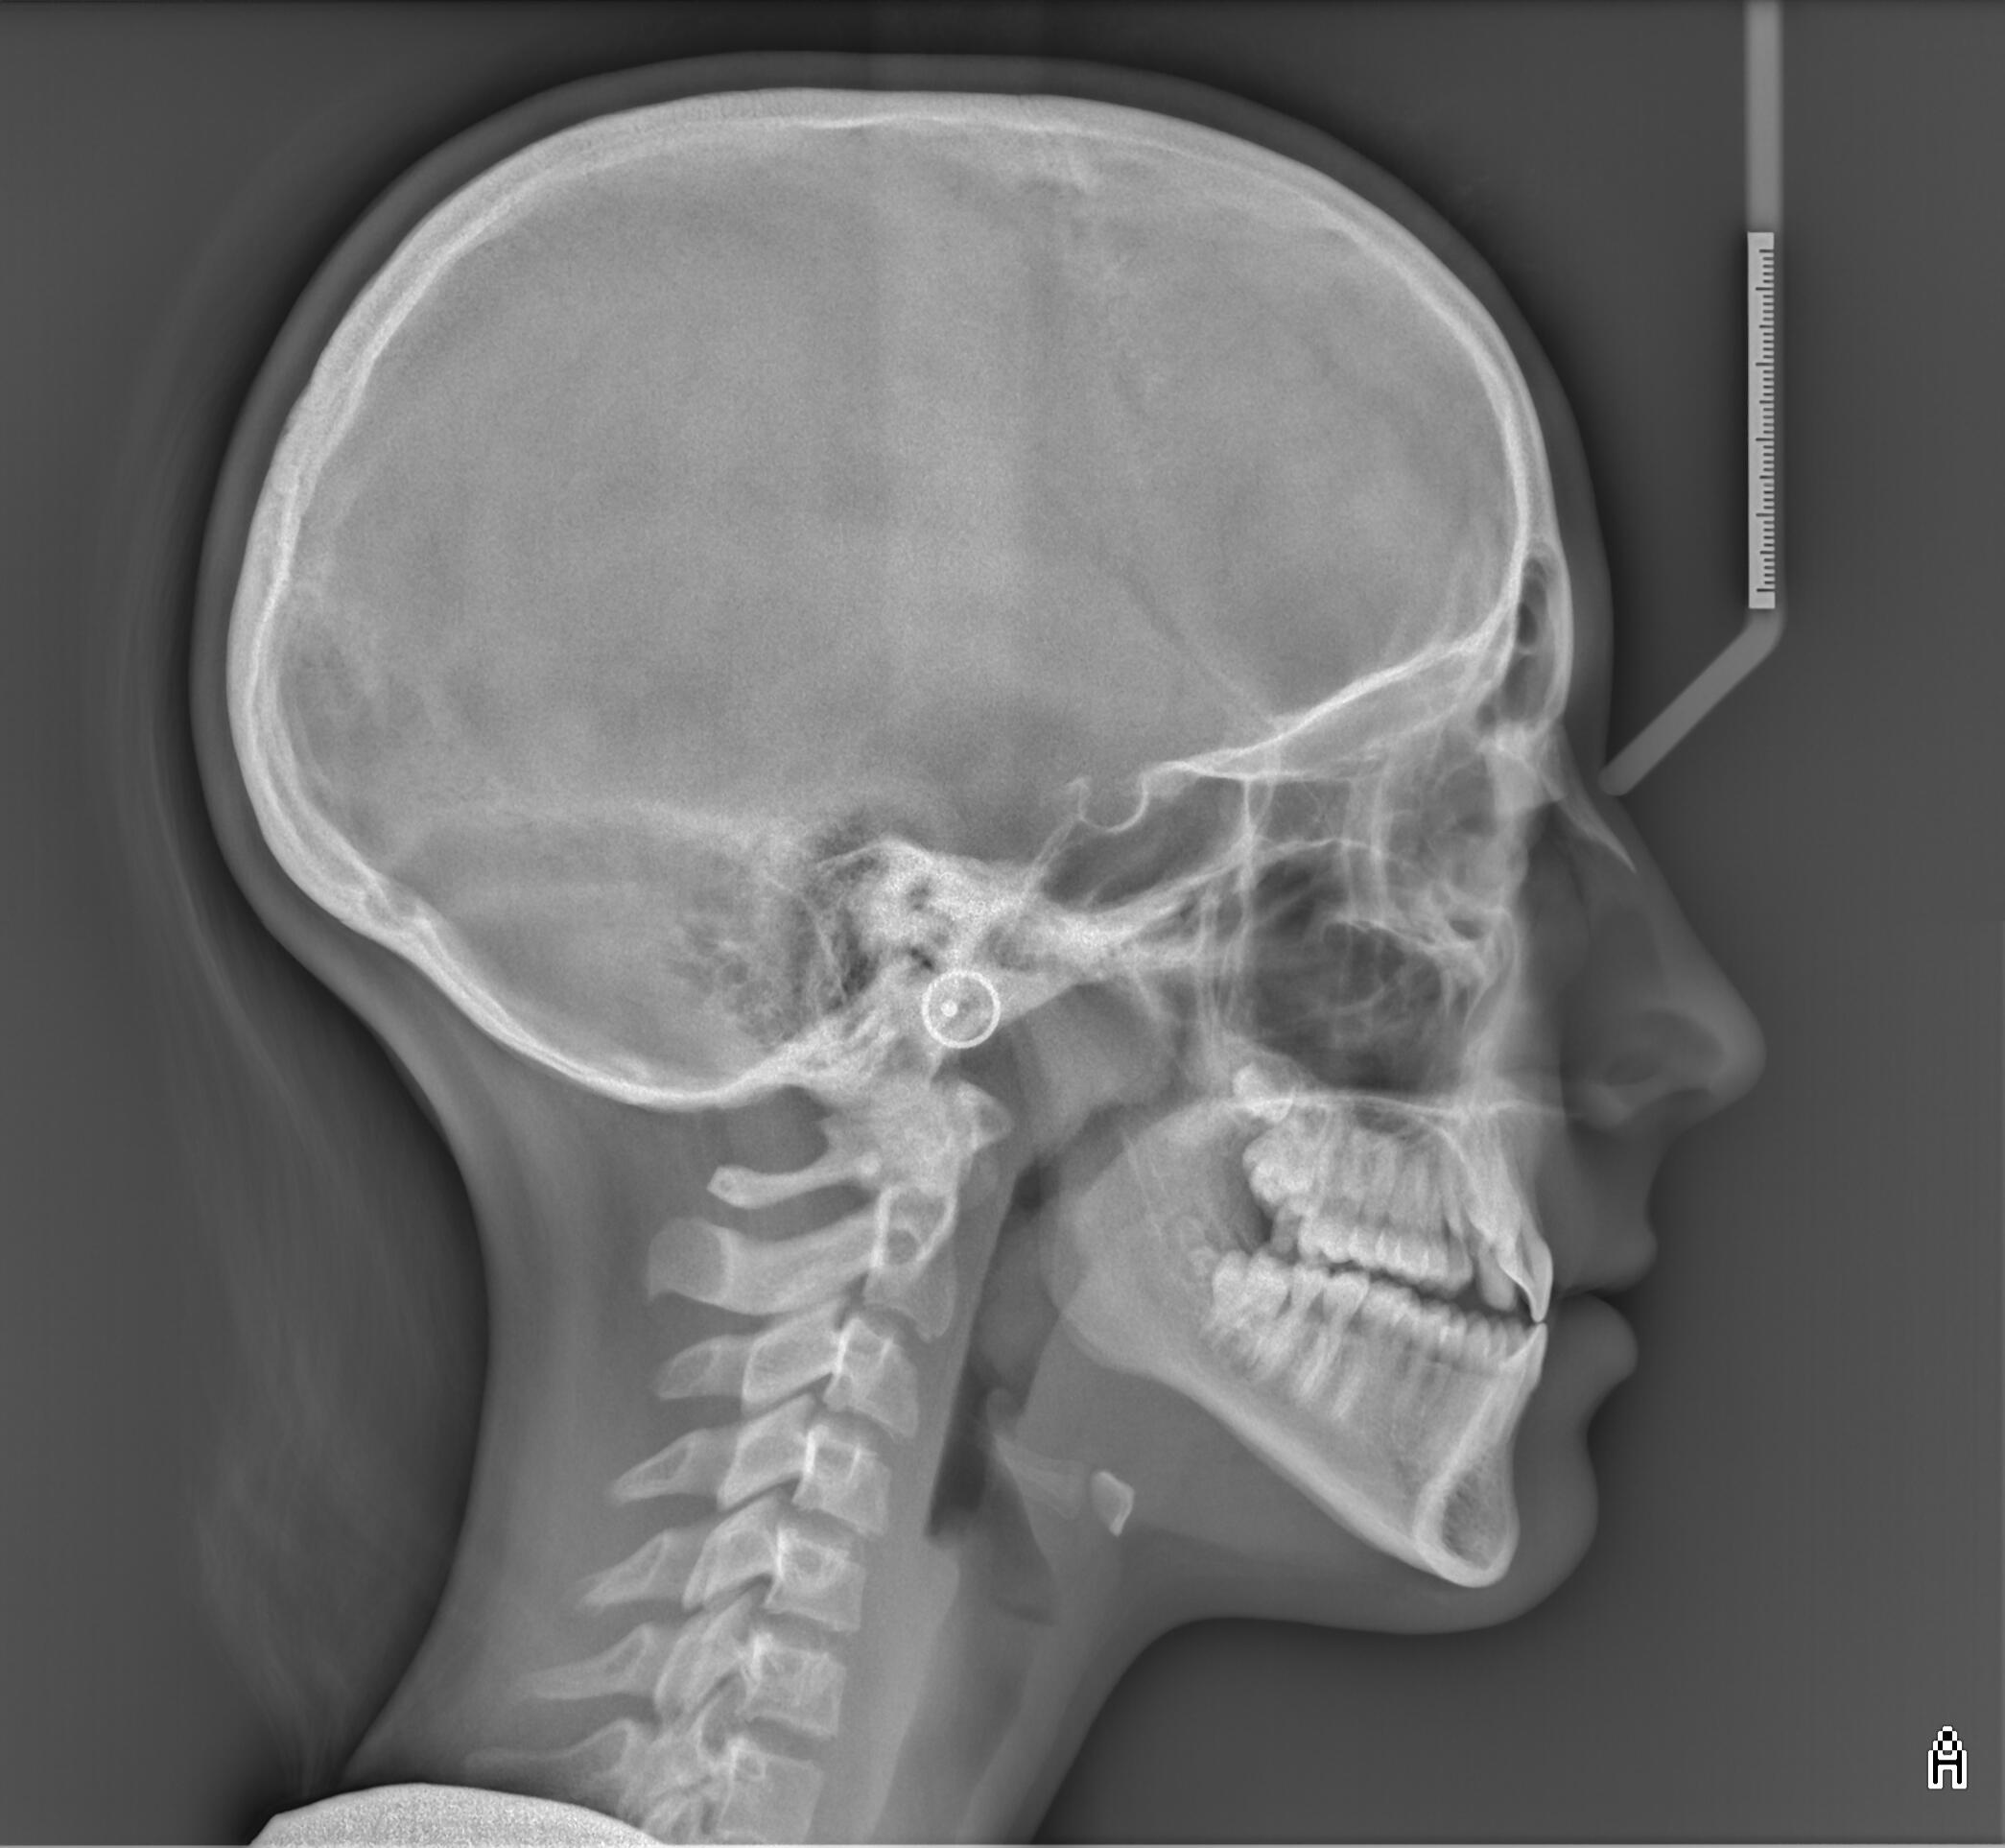

Телерентгенография

Planmeca ProMax 2D

Ортопантомограф, който се характеризира с:

- около 80% по-малко облъчване спрямо конвенционалните апарати.- намалено време за експонация при запазване на висока диагностична стойност на графиите.- възможност за изследване на пациенти в инвалидни колички.- телерентгенографии с отличен контраст и изобразяване на меките тъкани.